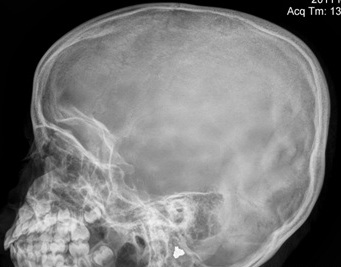

Langerhans cell histiocytosis is a multi system disorder with a certain predilection for involving hypothalamic pituitary axis. We hereby report a 7 year old girl presenting with polyuria, polydipsia and growth retardation. The girl had a past history of pain in right hip joint and nodular region over chest. Water deprivation test confirmed the diagnosis of central diabetes inspidus. Other investigations revealed Growth hormone deficiency and central hypothyroidism. X-ray and MRI hip revealed absent right inferior pubic ramus with bone marrow biopsy confirming the diagnosis of histiocytosis. Patient was treated with nasal Arginine Vasopressin spray, subcutaneous growth hormone and oral thyroxine.